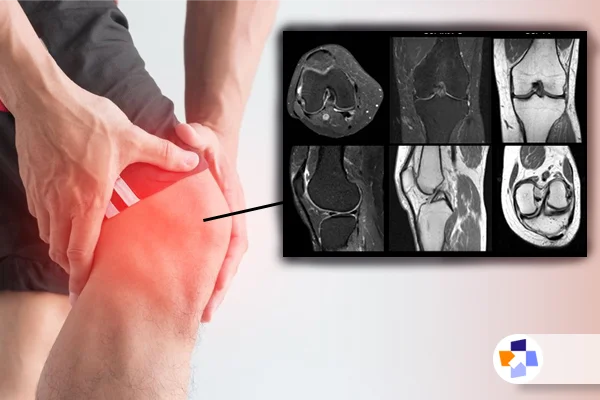

زانو یکی از مهمترین مفاصل بدن است که وظیفه پشتیبانی از حرکت و تحمل وزن بدن را بر عهده دارد. آسیبها و دردهای زانو میتوانند بهشدت بر کیفیت زندگی فرد تأثیر بگذارند، بهویژه اگر تشخیص و درمان مناسب بهموقع انجام نشود. در این میان، ام آر آی زانو یکی از معتبرترین و دقیقترین روشهای تشخیصی است که به پزشکان کمک میکند تا مشکلات پیچیده زانو را شناسایی کنند.

اگر شما هم درد یا مشکلاتی در زانو دارید و نمیدانید که آیا نیاز به درمان دارید یا خیر، ام آر آی زانو میتواند راهگشای بسیاری از سوالات شما باشد. در این مقاله، به طور کامل به بررسی اهمیت این روش تصویربرداری پرداخته و به شما توضیح خواهیم داد که چرا ام آر آی میتواند گزینهای بسیار مناسب برای شناسایی مشکلات مختلف زانو باشد. همچنین در ادامه با جزئیات نحوه انجام ام آر آی، آموزش خواندن ام آر آی، کاربردهای آن و روشهای تشخیص دقیقتر از طریق این مقاله در مجله طبی آشنا خواهید شد.

ام آر آی یک فرآیند ساده و بدون درد است که میتواند تصاویر دقیقی از داخل زانو ارائه دهد. این تست بدون استفاده از اشعه ایکس، بهوسیله میدان مغناطیسی و امواج رادیویی تصاویری دقیق از بافتهای نرم مانند رباطها، غضروفها و منیسکها ایجاد میکند. در این بخش، به مراحل مختلف انجام ام آر آی خواهیم پرداخت.

آموزش خواندن ام آر آی زانو؛ از دست ندهید

ام آر آی زانو، همانطور که قبلاً توضیح داده شد، یکی از دقیقترین روشها برای بررسی مشکلات زانو است. اما این تنها نصف ماجراست. بسیاری از بیماران و حتی برخی از پزشکان ممکن است برای درک دقیق تصاویر ام آر آی زانو نیاز به راهنمایی داشته باشند. در این بخش، قصد داریم نحوه خواندن تصاویر ام آر آی زانو را توضیح دهیم و شما را با اصطلاحات و نکات کلیدی آشنا کنیم.

1. آشنایی با تصاویر ام آر آی زانو

تصاویر ام آر آی (MRI) معمولاً بهصورت مقطعهای عرضی (cross-sectional) از داخل زانو بهدست میآیند که میتوانند اطلاعات دقیقی درباره بافتهای نرم مانند رباطها، منیسکها، غضروفها و مایع مفصلی فراهم کنند. در این تصاویر، هر قسمت با رنگهای مختلف نشان داده میشود:

- بافتهای نرم: مانند رباطها و منیسکها معمولاً به رنگ سفید یا خاکی دیده میشوند.

- استخوانها: استخوانها معمولاً سیاه و بدون جزئیات هستند زیرا امواج رادیویی به راحتی از استخوان عبور میکنند.

- مایع مفصلی: مایع مفصلی به رنگ تیره و سیاه دیده میشود و معمولاً در نواحی مفصل زانو قرار دارد.